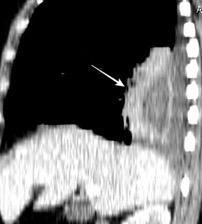

Marzo 2014: Perforación longitudinal distal secundaria a episodio de vómito (síndrome de Boerhaave). Derrame pleural izdo. que evoluciona a empiema.